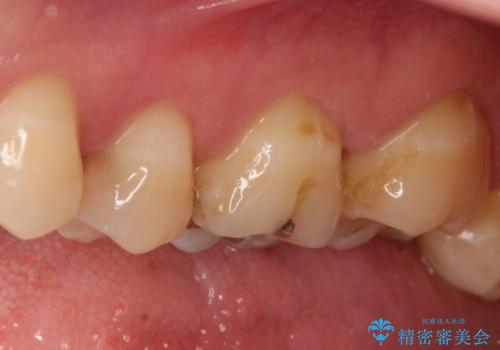

- 奥歯がズキズキ痛いことを主訴に来院されました。

治療にて歯髄は保存できないと判断したため、根管治療を行いセラミッククラウンにて修復しております。